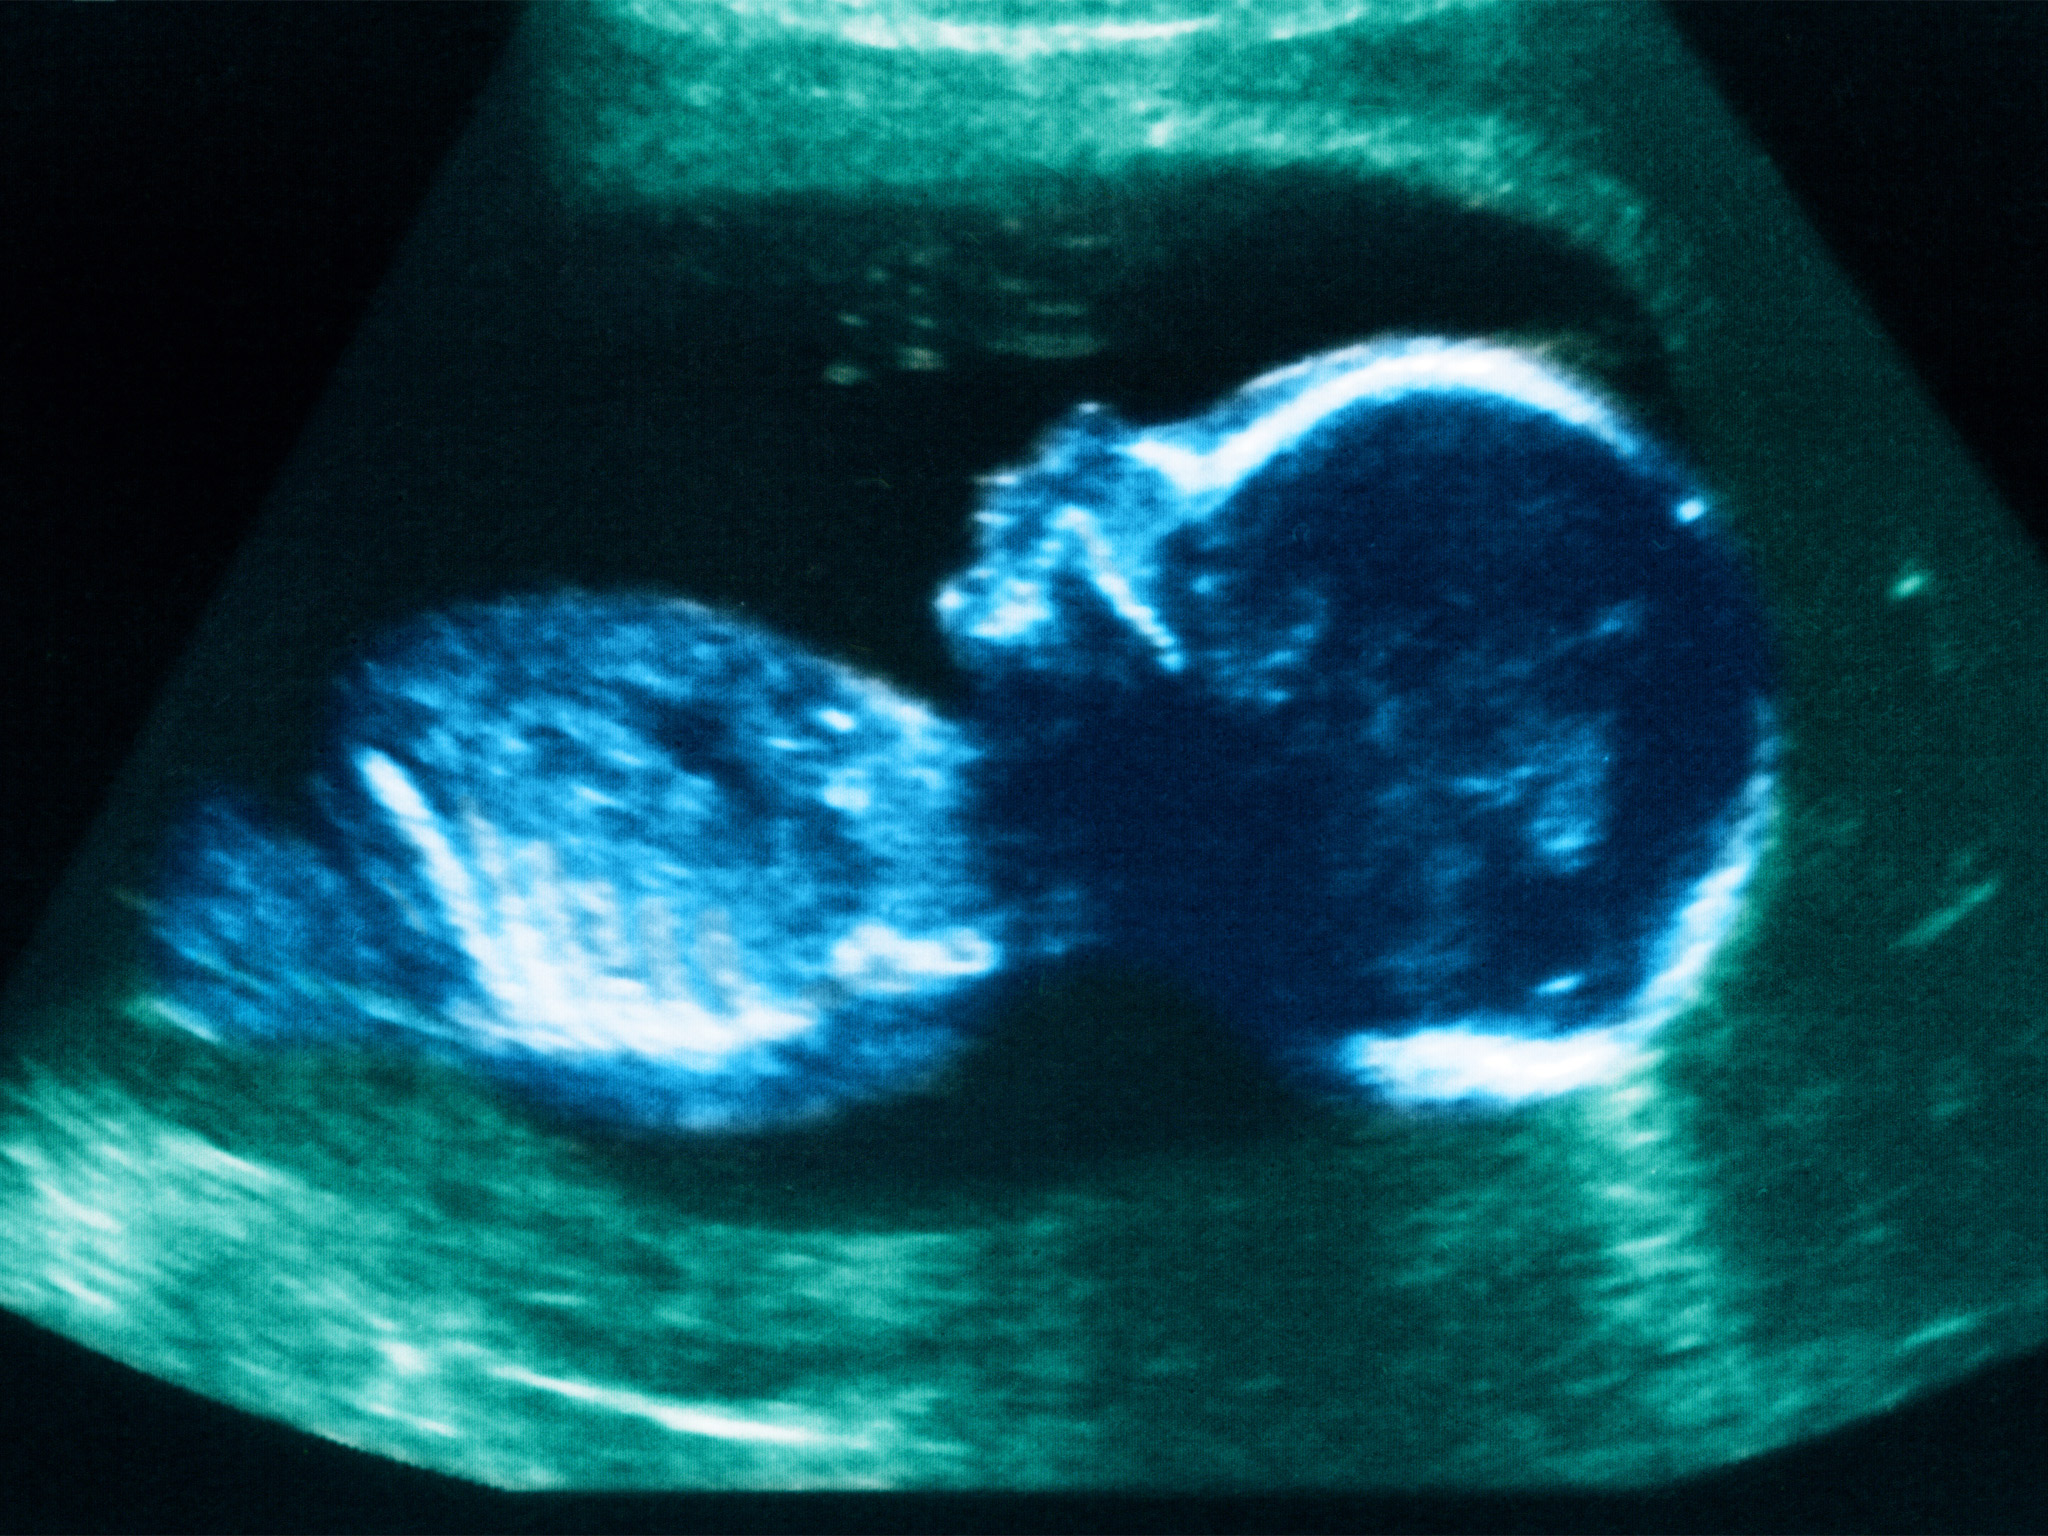

На 10 неделе беременности ваш малыш продолжает активно развиваться. Узи фотографии позволяют нам заглянуть внутрь и увидеть, как он выглядит на этом этапе.

Как выглядит ребенок на узи фото в 10 недель?

На этой стадии беременности ребенок становится все более осознанным и активным. Узи фотографии показывают, что его плодовой мешок становится уже образованным, а сердцебиение можно услышать с помощью узи аппарата.

Хотя пока еще рано говорить о половой принадлежности ребенка на узи фото, уже можно увидеть формирование его черт лица. Глаза, нос, губы - все более четко проглядывается на узи снимках.

Узи фотографии на 10 неделе беременности позволяют врачу и родителям отслеживать развитие ребенка и убедиться в его здоровье. Кроме того, они могут стать прекрасным сувениром для будущих родителей, чтобы сохранить воспоминания о начале этого незабываемого путешествия.

На каждом этапе беременности узи фотографии играют важную роль в мониторинге здоровья и развития ребенка. Они позволяют нам увидеть его рост, движения и формирование черт лица. Благодаря узи фото мы можем сопровождать малыша в его путешествии в мире материнства.